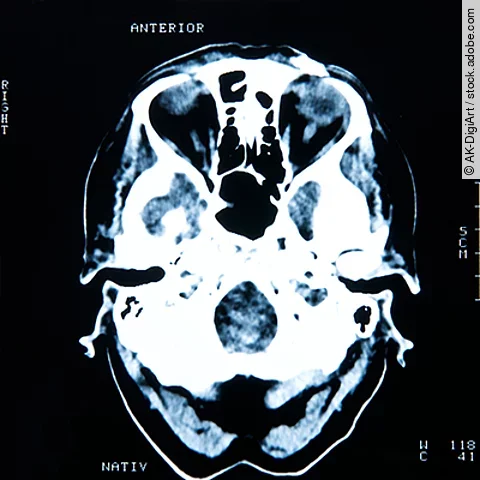

Mit der späteren Entwicklung von Hirntumoren verbunden waren mittelschwere oder schwere Schädel-Hirn-Traumata und ein penetrierendes Schädel-Hirn-Trauma, jedoch kein leichtes Schädel-Hirn-Trauma.

Erhöhen traumatische Hirnverletzungen das Risiko für einen Hirntumor? Diese Frage wird von Wissenschaftlern kontrovers diskutiert. Eine aktuelle Studie hat dies nun am Beispiel von Veteranen erforscht, die sich im Einsatz entsprechende Verletzungen zugezogen haben.